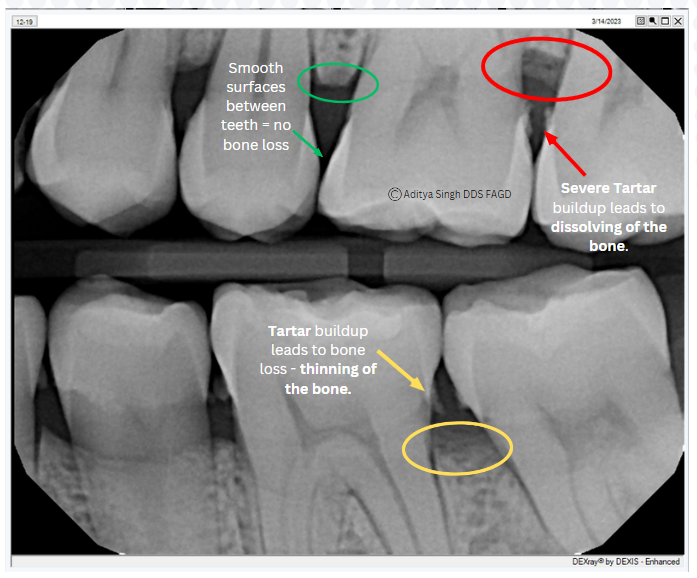

Gum disease is progressive, and without gingivitis treatment, the infection advances, and harmful bacteria and tartar deposits build up on teeth above and below the gumline. You can’t clean this area when you brush, and without treatment, you may experience bleeding, increased inflammation, receding gums, and loss of bone tissue. Here's am example of mild to moderate bone of from a patient's x-ray.